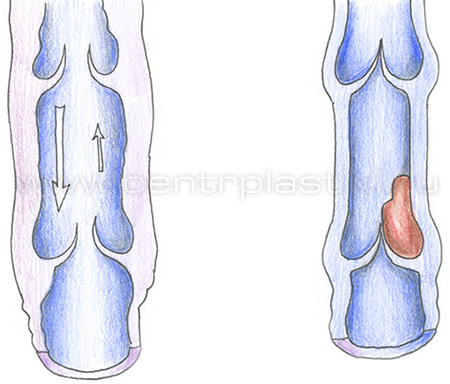

Варикоз - причины и механизмы развитияВарикозная болезнь – это полиэтиологическое заболевание, часто возникающее из-за генетической предрасположенности (так называемая слабость соединительной ткани), гормонального влияния (беременность, прием гормональных препаратов), конституции тела (чаще заболевают люди высокого роста и те, чья масса тела превышает норму), расовой принадлежности (например, варикозом редко страдают люди желтой и черной расы).  На возникновение заболевания существенно влияют образ жизни и характер трудовой деятельности («стоячая» работа, тяжелые физические нагрузки, частое ношение высоких каблуков).  Все этиологические факторы варикоза условно делятся на две группы: предрасполагающие и производящие. Предрасполагающими факторами называют те, что влияют на морфологические и функциональные изменения стенок поверхностных вен и клапанов. Эти факторы сами по себе не приводят к расширению вен, но создают условия, в которых образуется анатомическая и функциональная неполноценность системы поверхностных вен ног.  Производящие факторы представляют собой многочисленную группу, и среди них выделяют три ведущих механизма, ответственных за венозную гипертензию нижних конечностей: 1. Нарушение оттока крови из венозной системы нижних конечностей (из-за высокого роста, статической нагрузки, внутрибрюшного давления, кашля, запора, беременности). 2. Переход крови из глубоких вен в поверхностные приводит к расширению глубоких вен, что влечет за собой относительную клапанную недостаточность и варикоз поверхностных вен. 3. Переход крови из системы артериального кровотока в поверхностные вены по артериовенозным коммуникациям, которые в нормальном состоянии не функционируют, а служат лишь для ситуаций тяжелой мышечной работы, действия высокой температуры, и т.д.). В настоящее время механизмы повреждения стенок вен при варикозе объясняются при помощи феномена лейкоцитарной агрессии. При гипертензии нормальная вена, которая обладает значительным резервом возможностей, реагирует на изменение ситуации повышением своего тонуса. Если же возникла врожденная или приобретенная слабость венозной стенки и просвет вены необратимо увеличился, то этого не происходит. Современные представления о механизмах повреждения стенки вены при варикозной болезни основываются на феномене лейкоцитарной агрессии. Нормальная вена, обладая значительными резервными возможностями, реагирует на гипертензию повышением своего тонуса. Этого не происходит при врожденной или приобретенной слабости мышечно-эластических образований венозной стенки, когда в ответ на периодическое или постоянное повышение внутрисосудистого давления постепенно развивается необратимое увеличение просвета вены.  1 - Макрофаг; 2 - Миграция и адгезия макрофага; 3 - Клапанный синус; 4 - Молекулярная экспрессия; 5 - Проксимальный отдел вены; 6 - Нижняя поверхность створки клапана; 7 - Венозный клапан; 8 - Дистальный отдел вены; 9 - Венозная стенка. Замедление кровотока приводит к краевому стоянию лейкоцитов, которое происходит из-за их плотного контакта с эндотелийным слоем, на поверхности которого начинают экспрессироваться адгезивные молекулы, деятельность которых стимулируется медиаторами воспаления. В результате образуется хронический процесс воспаления, к которому присоединяется патогенная микрофлора и развитие инфекции. Стенка варикозной вены теряет тканевый активатор плазминоген, это снижает местную фибринолитическую активность, возрастает риск спонтанного тромбообразования и развития острого варикотромбофлебита. Повышается проницаемость капиллярной системы и внутрикапиллярное давление, это приводит к просачиванию из сосудистого русла в ткани не только воды, электролитов, и различных белковых фракций, но и форменных элементов крови. Геморрагическое пропитывание усиливает склеротические процессы в тканях и служит причиной возникновения характерной гиперпигментации кожи.  Флебостаз усиливает сопротивление венозного конца капиллярного русла, лимфатические капилляры перегружаются, происходит расширение лимфатических сосудов, объем оттекающей лимфы увеличивается. Лимфатическая система оказывается неспособна к достаточному дополнительному дренажу из тканей пораженной конечности: развивается отек, а белки плазмы и лейкоциты проникают в околососудистые ткани. Возникает процесс полимеризации фибриногена вокруг капилляров, происходит возникновение периваскулярных фибриновых муфт, которые ещё больше нарушают трофику и способствуют развитию язв. Местные медиаторы воспаления провоцируют появление разнообразных аутоаллергических реакций, которые провоцируют склерозирующий лимфангоит. Сосуды лимфы перестают ритмически сокращаться и становятся неподвижными трубками. Стенки сосудов становятся более проницаемыми, сквозь них в окружающие ткани просачивается богатая белками лимфа, развивается фиброз. Отек становится все более и более стойким и может превратиться во флебогенную слоновость. Также нарушается центральная гемодинамика, поскольку в варикозно-деформированных венах содержится от 1,5 до 3-х литров крови. Это ведет возникновения компенсаторного увеличения ОЦК (гиперволемии) и перегрузке венозного русла. Миокард изменяет свое функционирование, поскольку при ортостазе, если снижается сердечный индекс, то отсутствует компенсация его тахикардией, а это ведет за собой недостаточность системного кровообращения. При отсутствии лечения варикоз переходит в стадию трофических изменений мягких тканей ног вплоть до образования трофических язв. |